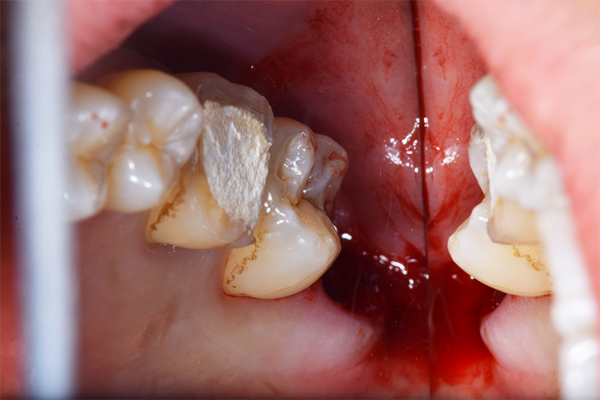

上顎の親知らずの抜歯のBefore/Afterです。抜歯時間は10分です。上顎の抜歯はほとんど腫れることもないです。リスクとしては一番最初の症例のように上顎洞への穿孔です。ただし、穿孔したとしても、鼻をつよくかむなどせず、安静にしていれば、しっかり回復しますので安心してください。抜歯費用は約1,700円(保険適応)

です。